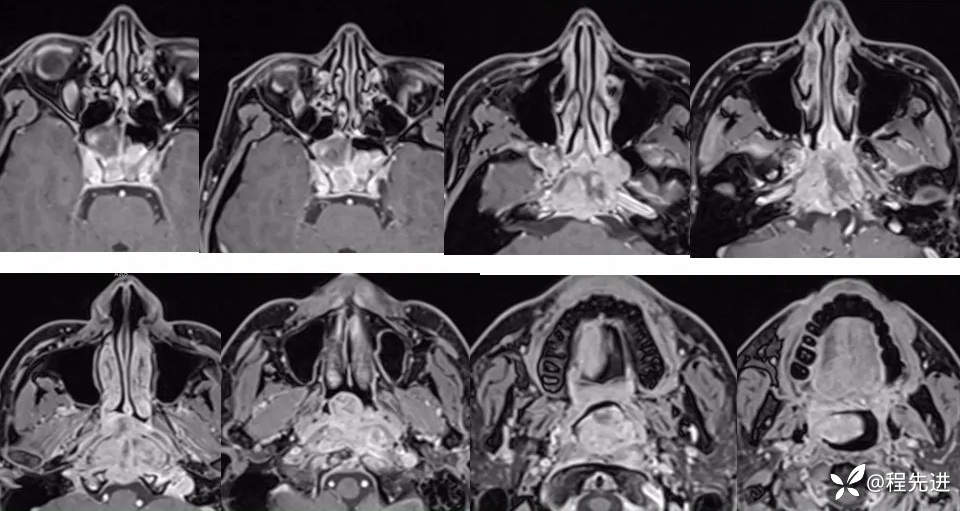

【面颈】特别精彩病例|睡眠打鼾半年,颅底占位期待您的精彩解读!

现病史:半年前无明显诱因出现睡眠打鼾,张口呼吸,2个月前出现间断性双鼻塞,出现说话含薯音,痰中带血,无流涕。外院内镜检查示“鼻咽部肿物”,取病理为“鼻咽部混合瘤”,不除外恶变。病来无鼻出血,无面部麻,无牙齿疼痛,无呼吸困难,无颈部淋巴结肿大。近来无发热,精神体力可,食睡二便可,体重2个月来下降5千克。

T1、T2: